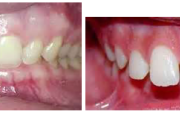

Vali sind huvitav pilt ja me näitame sellega seotud haigust ja sümptomeid